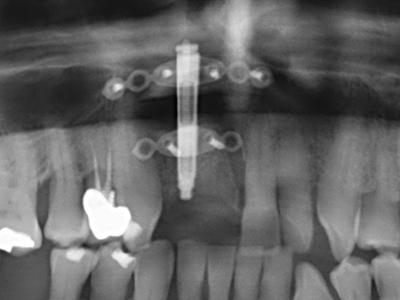

Fig. 13: Adequate irrigation with the 4-mm residual bone width is essential for this 52-year-old patient during the bone splitting.

Fig. 14: Placement of four tapered RSX implants (Bego Implant Systems, Bremen).

Fig. 15: The one-year follow-up x-ray examination shows stable conditions at the bone level.